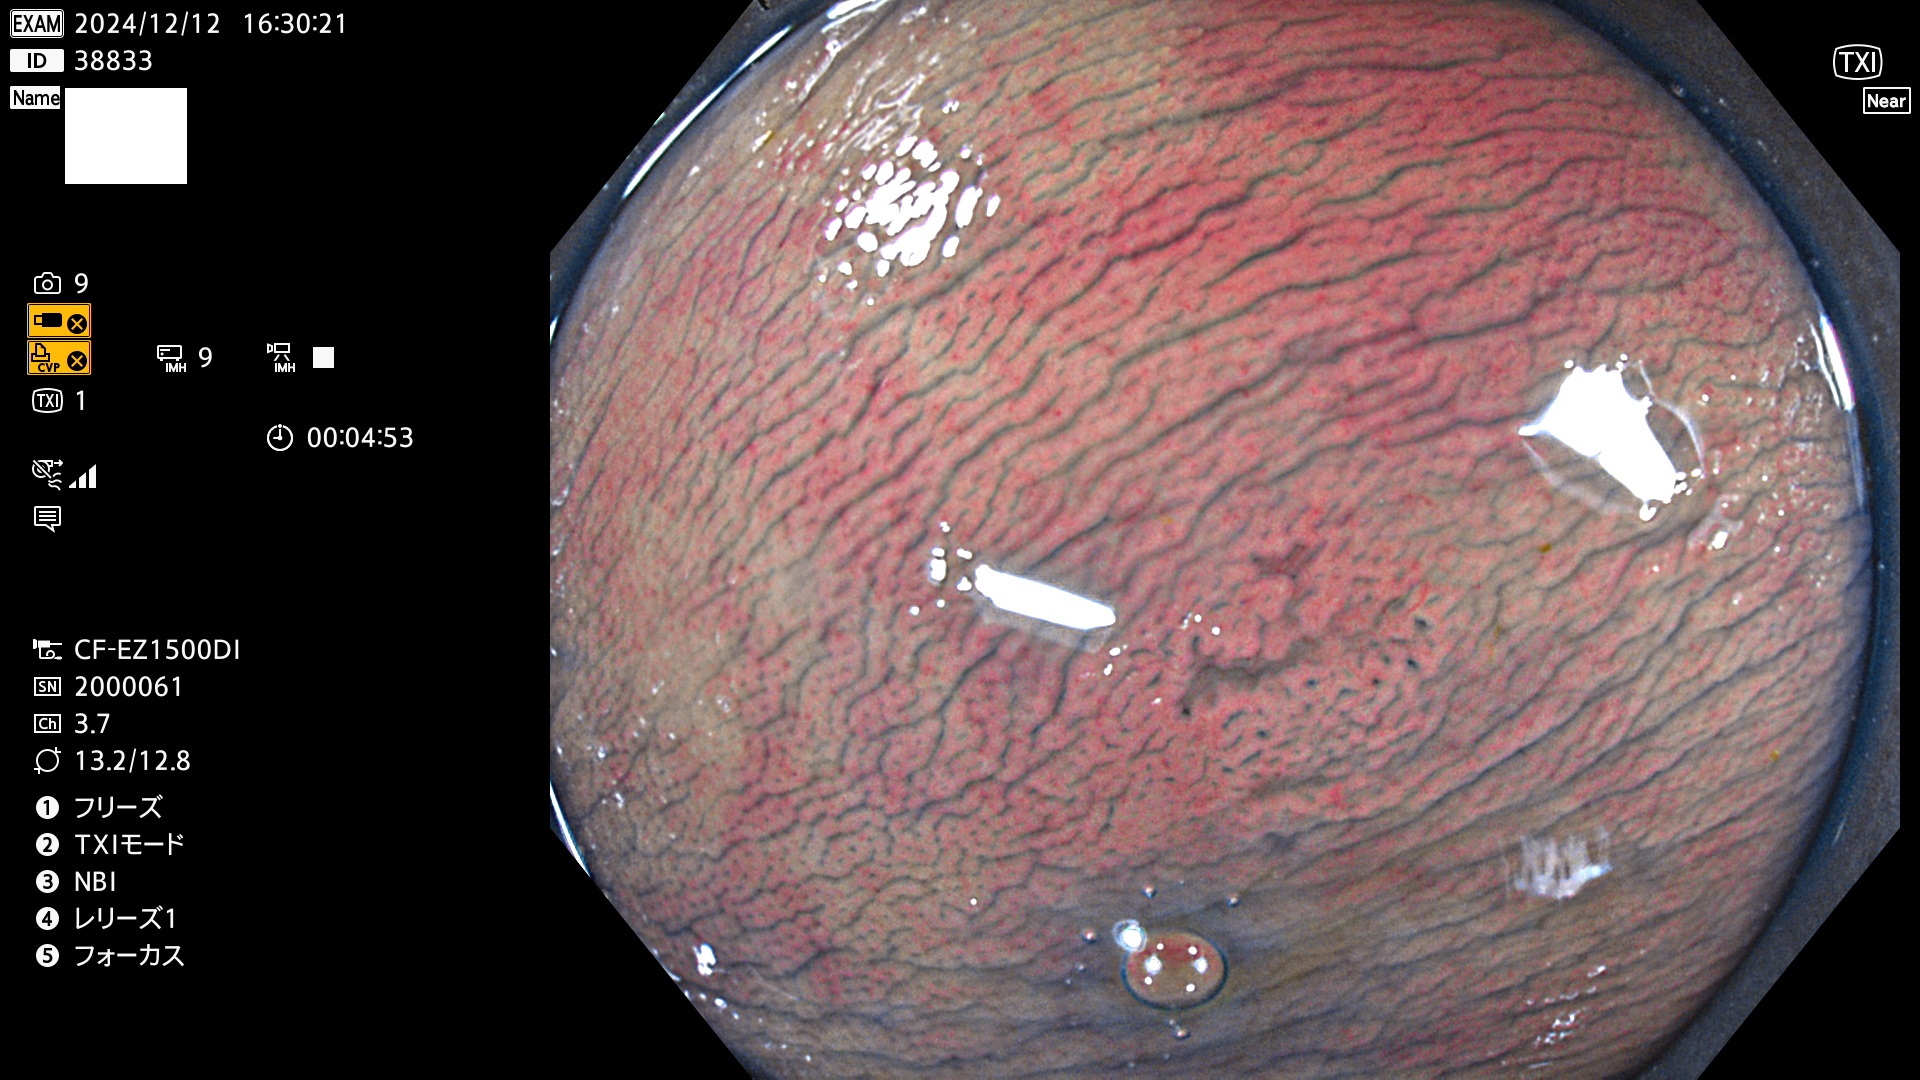

完全に平坦な物をUb、陥凹している物をUcと呼びます。最も発見が難しく危険な病変です。

毎週の検査(木・金・土・日)に発見されたUb、Uc型・腺腫を、その週の日曜の夜にUPし1週間、提示します。

抽出の対象期間 2024年12月12日〜12月16日の5日間(60件の検査)13件 (13/60=21%)